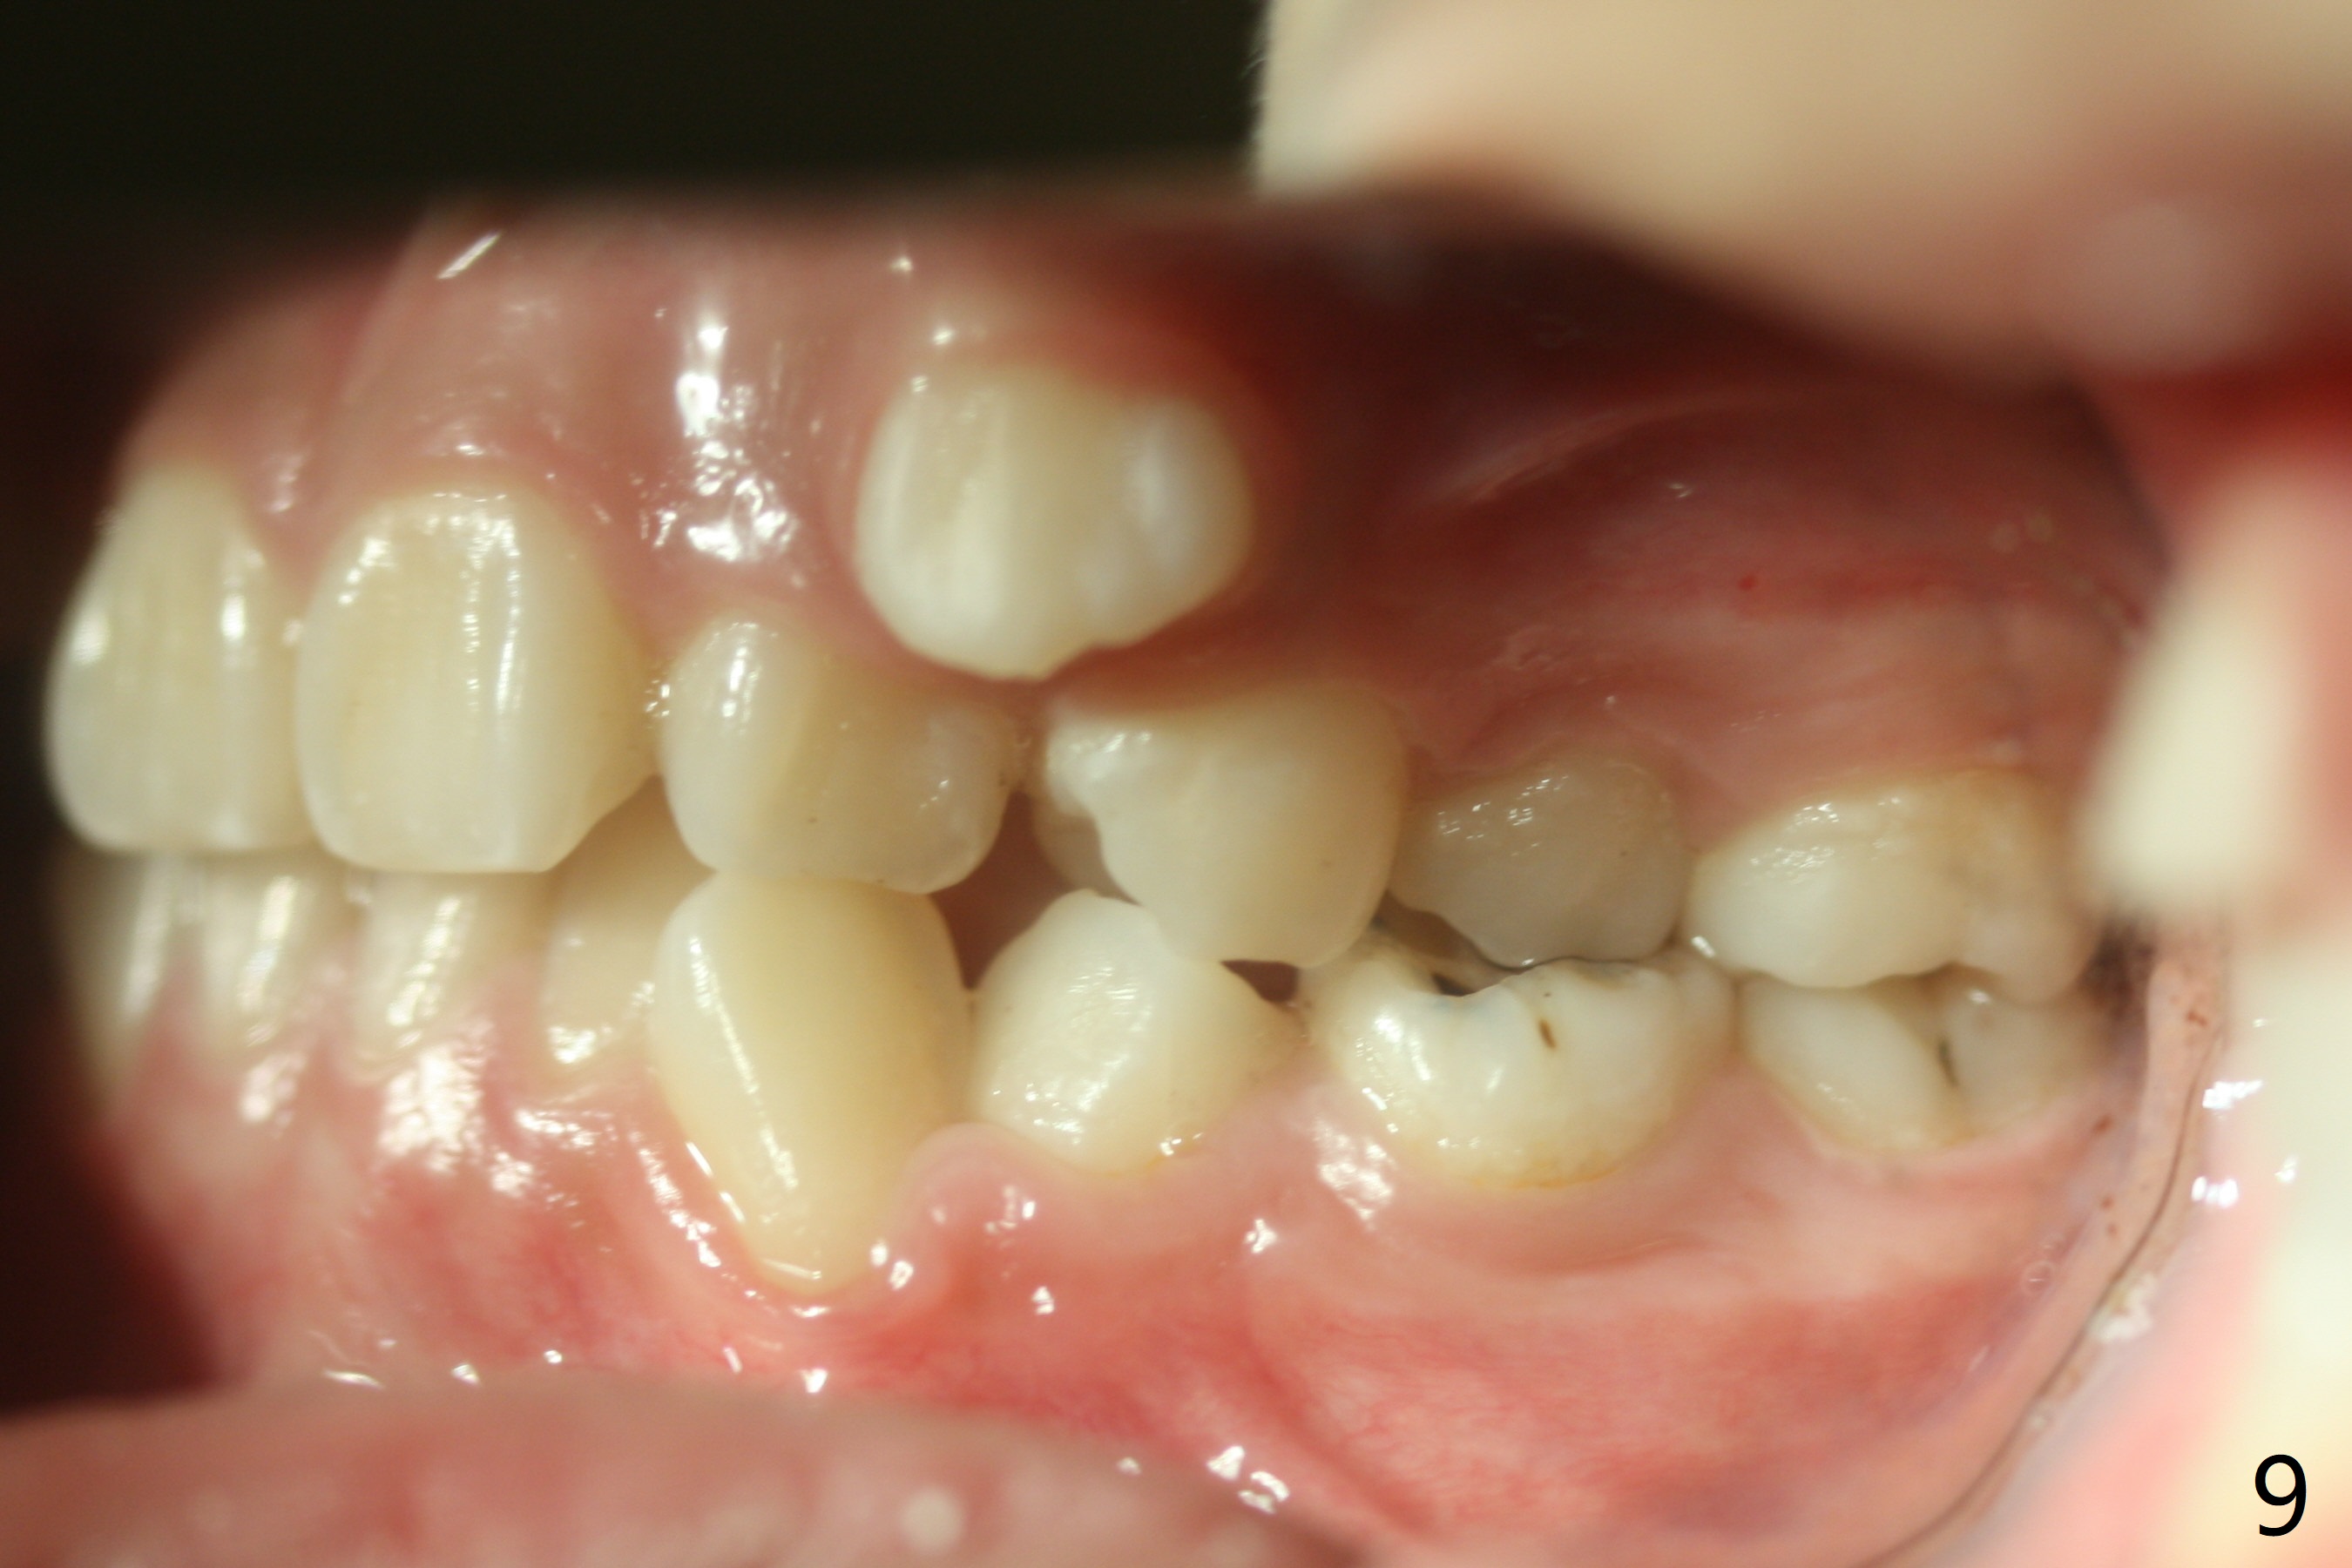

Severe crowding with normal facial profile appears to dictate extraction of 4 bicuspids and of the lower 2nd primary molars (Fig.1-11).  Since there is no time for banding before school, delay in orthodontic treatment post extraction will lose space?

Dear Dr. Shaughnessy: can you open the following link?  I would like to try to extract 4 bicuspids and 2 lower primary 2nd molars and let the canines shift by themselves.  But I wonder whether the 2nd permanent bicuspids, especially the upper ones, may shift mesially instead.  How would you like to handle the situation?